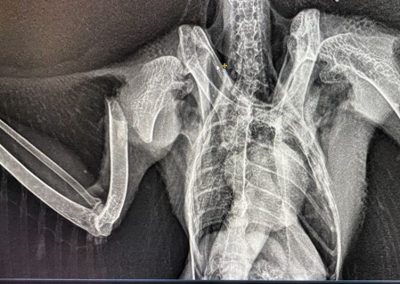

In unserer modernen, verbauten Welt ist der Luftraum kein sicherer Ort mehr. Was für uns Fortschritt und Infrastruktur bedeutet, wird für Eulen, Greif- und Wasservögel oft zur tödlichen Falle. Eine Wildvogelstation ist weit mehr als nur ein Ort für die Aufzucht flauschiger Küken – sie ist ein Lazarett an der vordersten Front.

Die Verletzungen, die wir täglich behandeln, sind keine Unfälle der Natur. Sie sind die direkten Folgen unseres menschlichen Wirkens:

• Infrastruktur-Opfer: Anflüge gegen Hochspannungsleitungen und die rotierenden Schaufeln von Windrädern sorgen für schwerste Traumata und Amputationen

• Tödliche Barrieren: Stacheldraht zerschneidet Schwingen; Glasfronten und der Straßenverkehr führen zu massiven inneren Verletzungen und Knochenbrüchen.

Die folgenden Bilder zeigen ungeschönt den Alltag in der medizinischen Notversorgung. Sie sehen Blut, offene Wunden und chirurgische Eingriffe. Das ist die notwendige, harte Arbeit hinter den Kulissen. Wir kämpfen um jedes Leben – mit Skalpell, Verband und fachmedizinischer Expertise –, um die Fehler wiedergutzumachen, die unsere Zivilisation verursacht hat.

Die folgenden Aufnahmen sind nichts für schwache Nerven. Sie zeigen Blut, offene Frakturen und den harten Kampf im Operationssaal. Wir zeigen sie bewusst. Denn diese Bilder sind die ungeschönte Antwort auf unsere Art zu leben.

Hinter jedem Foto steht ein Schicksal, ein Kampf und unser unermüdlicher Einsatz, das Unrecht der Zivilisation medizinisch zu korrigieren.